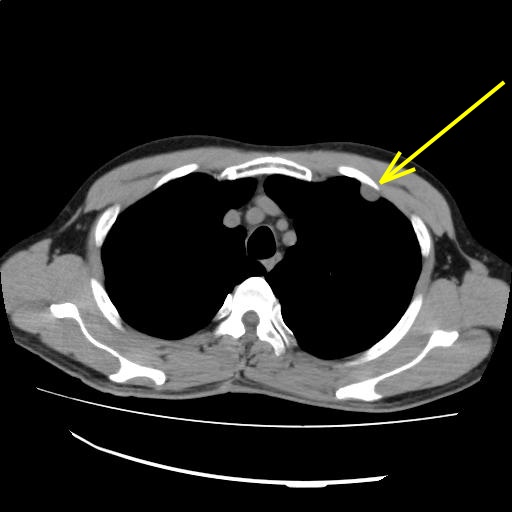

1.胸水を認める

【画像診断検査結果】

(Findings)

左第2肋骨沿いに神経鞘腫を疑う腫瘤を認めるが、サイズおよび形状に著変なし。

右上葉末梢の小石灰化に著変なし。

肺野に新規病変を認めない。

縦隔および肺門リンパ節に病的腫大を認めない。

胸水を認めない。

肝嚢胞を認める。

左腎嚢胞を認める。

胆嚢、膵、脾、副腎に著変なし。

傍大動脈領域にリンパ節の病的腫大を認めない。

腹水を認めない。

(Impression)

左胸壁腫瘤:前回と著変なし